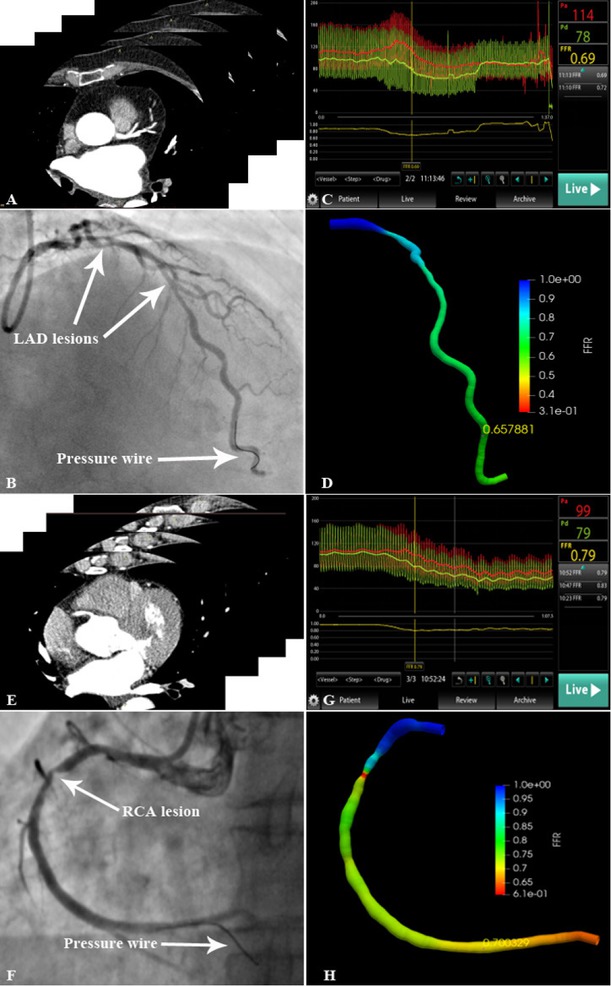

Once all CCTA and CAG images had been acquired, the calculation of FFRCT-angio was very fast (120 ± 13 s) due to the deep learning-based approach, for which the complex computation had been done in the training stage. Our results showed a high degree of correlation (r = 0.81; P < 0.001) and agreement (mean difference: 0.03 ± 0.08, 95% limit of agreement: -0.12–0.19) between FFRCT-angio and FFR values (Figure 3). Representative cases are displayed in Figure 4. Clinical discordance of FFR > 0.80 and FFRCT-angio ≤ 0.80 occurred in five vessels, whereas there was no occurrence of FFR ≤ 0.80 and FFRCT-angio > 0.80.

Representative lesions assessed by invasive FFR and FFRCT-angio (A) CCTA scan of LAD. (B) LAD lesion and pressure wire location are shown in the angiogram. (C) The FFR value measured using the pressure wire was 0.69. (D) 3D reconstruction of the LAD based on the integration of CAG and CCTA images. The FFRCT-angio value was highly correlated with the FFR value (FFRCT-angio = 0.66). (E) CCTA scan of RCA. (F) RCA lesion and pressure wire location are shown in the angiogram. (G) The FFR value measured using the pressure wire was 0.79. (H) 3D reconstruction of the RCA based on the integration of CAG and CCTA images. The FFRCT-angio value was highly correlated with the FFR value (FFRCT-angio = 0.70). CAG: coronary angiography; CCTA: coronary CT angiography; FFR: fractional flow reserve; LAD: left anterior descending artery; FFRCT-angio: fractional flow reserve derived from integrated CT angiography and invasive angiography; RCA: right coronary artery; 3D: three dimensional.